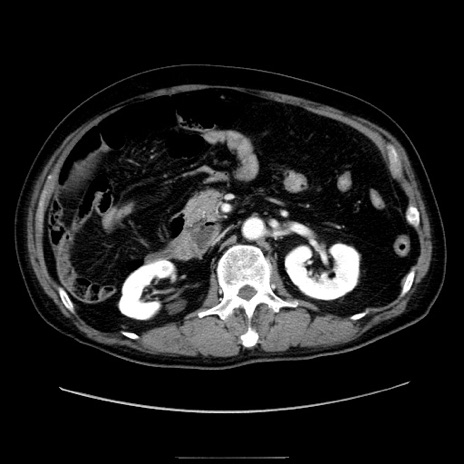

症例30(横断像)

【症例】80歳代男性

【主訴】臍周囲痛

【現病歴】約6時間前から臍下部痛が出現。次第に腹部膨隆・背部痛も生じてきたため来院。背部痛の場所は変化しない。

【身体所見】意識清明、BT 36.3℃、BP  131/87mmHg、P 87bpm、SpO2 100%(RA)、臍周囲自発痛・圧痛あり、反跳痛なし、自発痛部位に一致して板状硬あり、腹部膨隆、腸雑音減弱、CVA tenderness両側陰性。

【データ】WBC 19600、CRP 0.33